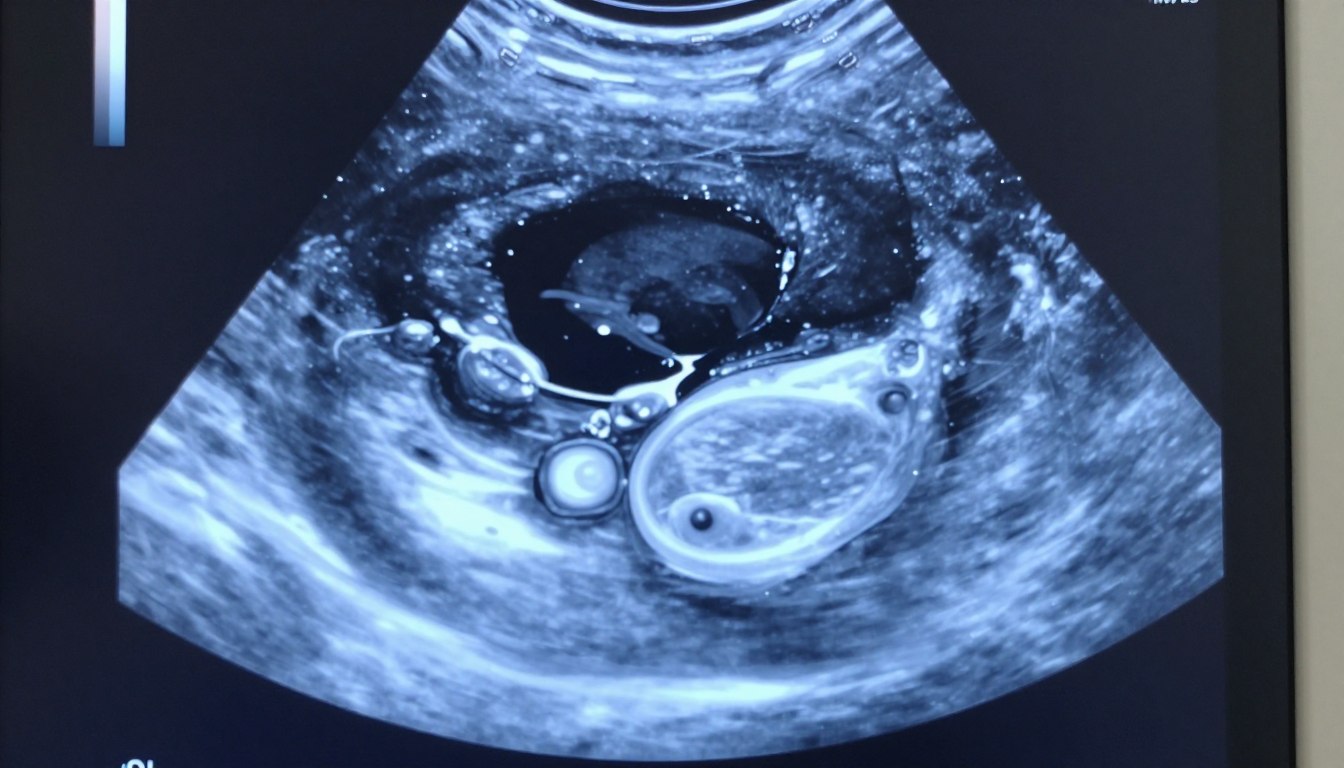

Czy wynik badania może zaskoczyć i jednocześnie nie oznaczać końca świata? To częste pytanie pacjentek, gdy w opisie pojawia się informacja o zmianie. W tym…